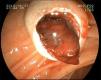

Paciente de 64 años, que ingresa en la unidad de cuidados intensivos por hemorragia digestiva persistente con altos requerimientos transfusionales y repercusión hemodinámica, tras consultar por dolor abdominal e ictericia obstructiva. Mediante estudio endoscópico se objetiva un gran coágulo impactado en la papila (fig. 1). En el estudio angiográfico (fig. 2) se observa arteria mesentérica superior desde la que parte la arteria hepática derecha, rotura de una rama principal de esta última, que se cierra con 19mm de coils fibrados y Spongostan®. La hemobilia masiva es una causa rara pero potencialmente fatal de hemorragia digestiva. El diagnóstico es endoscópico y la embolización transarterial es la opción terapéutica de elección. Las causas más habituales son postraumáticas o posquirúrgicas, tumores y malformaciones vasculares o aneurismas, siendo excepcionales aquellas en las que la causa subyacente no llega a encontrarse.